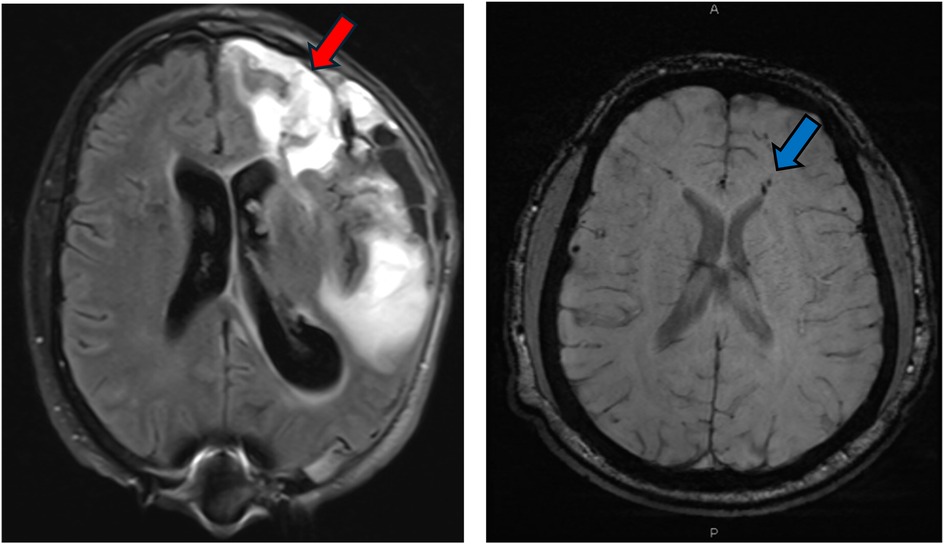

Mr. JP is a 60-year-old right-handed gentleman with a previous history of traumatic brain injury (age 52, left temporal intraparenchymal hemorrhage and left orbital roof fracture) who sustained a sTBI at age 59 following an unhelmeted motorcycle accident. His injuries were significant, including an extensive left frontotemporal hemorrhagic contusion, multicompartmental hemorrhages, subarachnoid hemorrhage, subdural hematoma, and a right sigmoid sinus thrombus (Figure 2). He also had abnormal EEGs with epileptiform abnormalities. His acute management involved decompressive hemicraniectomy, followed by cranioplasty in January 2020. He also sustained orthopedic injuries, including a right scapular fracture and left tibial and fibular fractures, requiring open reduction and internal fixation (ORIF).

Figure 2. MRI FLAIR sequence demonstrating significant multicompartmental intraparenchymal hemorrhage (red arrow) post decompressive left hemicraniectomy for patient JP. MRI SWI sequence demonstrating multiple foci of intraparenchymal hemorrhages and diffuse axonal injury (DAI) for patient JS (blue arrow).

Mr. JS is a 30-year-old right-handed male with a longstanding history of medically refractory epilepsy, initially diagnosed at age 14, and a more recent history of sTBI sustained after being struck by a motor vehicle while riding a scooter His epilepsy history includes generalized tonic-clonic seizures (GTCs), with the first documented seizure occurring in 2008, involving convulsive activity, drooling, unresponsiveness, and postictal confusion. Despite initial treatment with Depakote and subsequent trials of Keppra XR, Topamax, and Tegretol, Mr. JS continued to experience seizures, which later evolved into predominantly nocturnal events characterized by leftward eye deviation, gasping sounds, facial twitching, limb stiffening, and postictal aphasia. Prior to his initial neurocognitive assessment, he was experiencing seizures two to three nights per week, though there were periods of remission. Mr. JS sustained a severe TBI. He reported being stationary at a red light with no memory of the collision, regaining awareness in the hospital. Acute injuries included a right-sided subarachnoid hemorrhage (Figure 2), multiple orthopedic fractures (pubic rami, patella, femur, sternum, ribs, and hand), and a prolonged ICU and rehabilitation course. Surgical interventions involved multiple orthopedic repairs and wound closures.